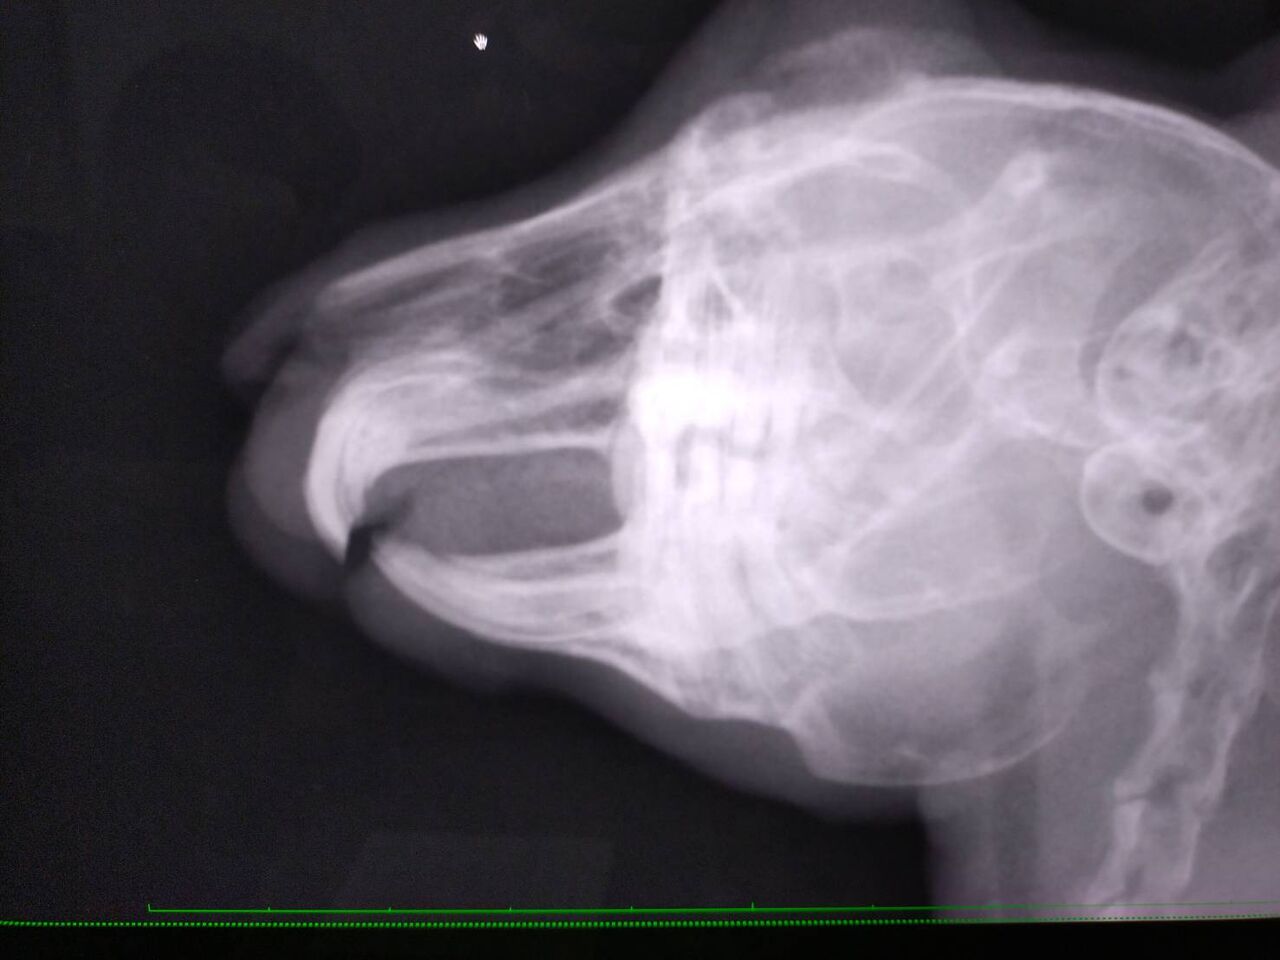

9/7 去勢手術 口腔内検査も一緒に行いました。

臼歯左上手前から2番目、左下1.2.4番目 外側に少し尖っている歯があり、念の為カットしました。